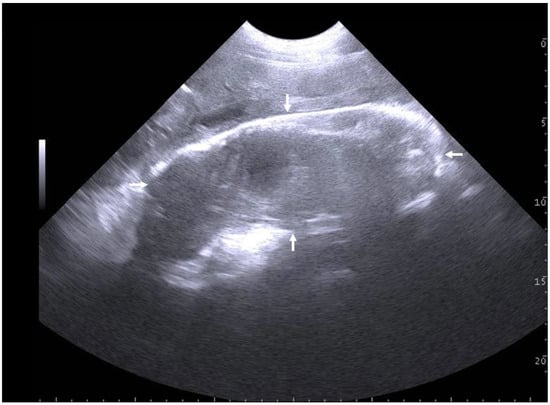

3.1.2. The Puerperal Uterus

3.1.3. The Non-Gravid Post-Puerperal Uterus